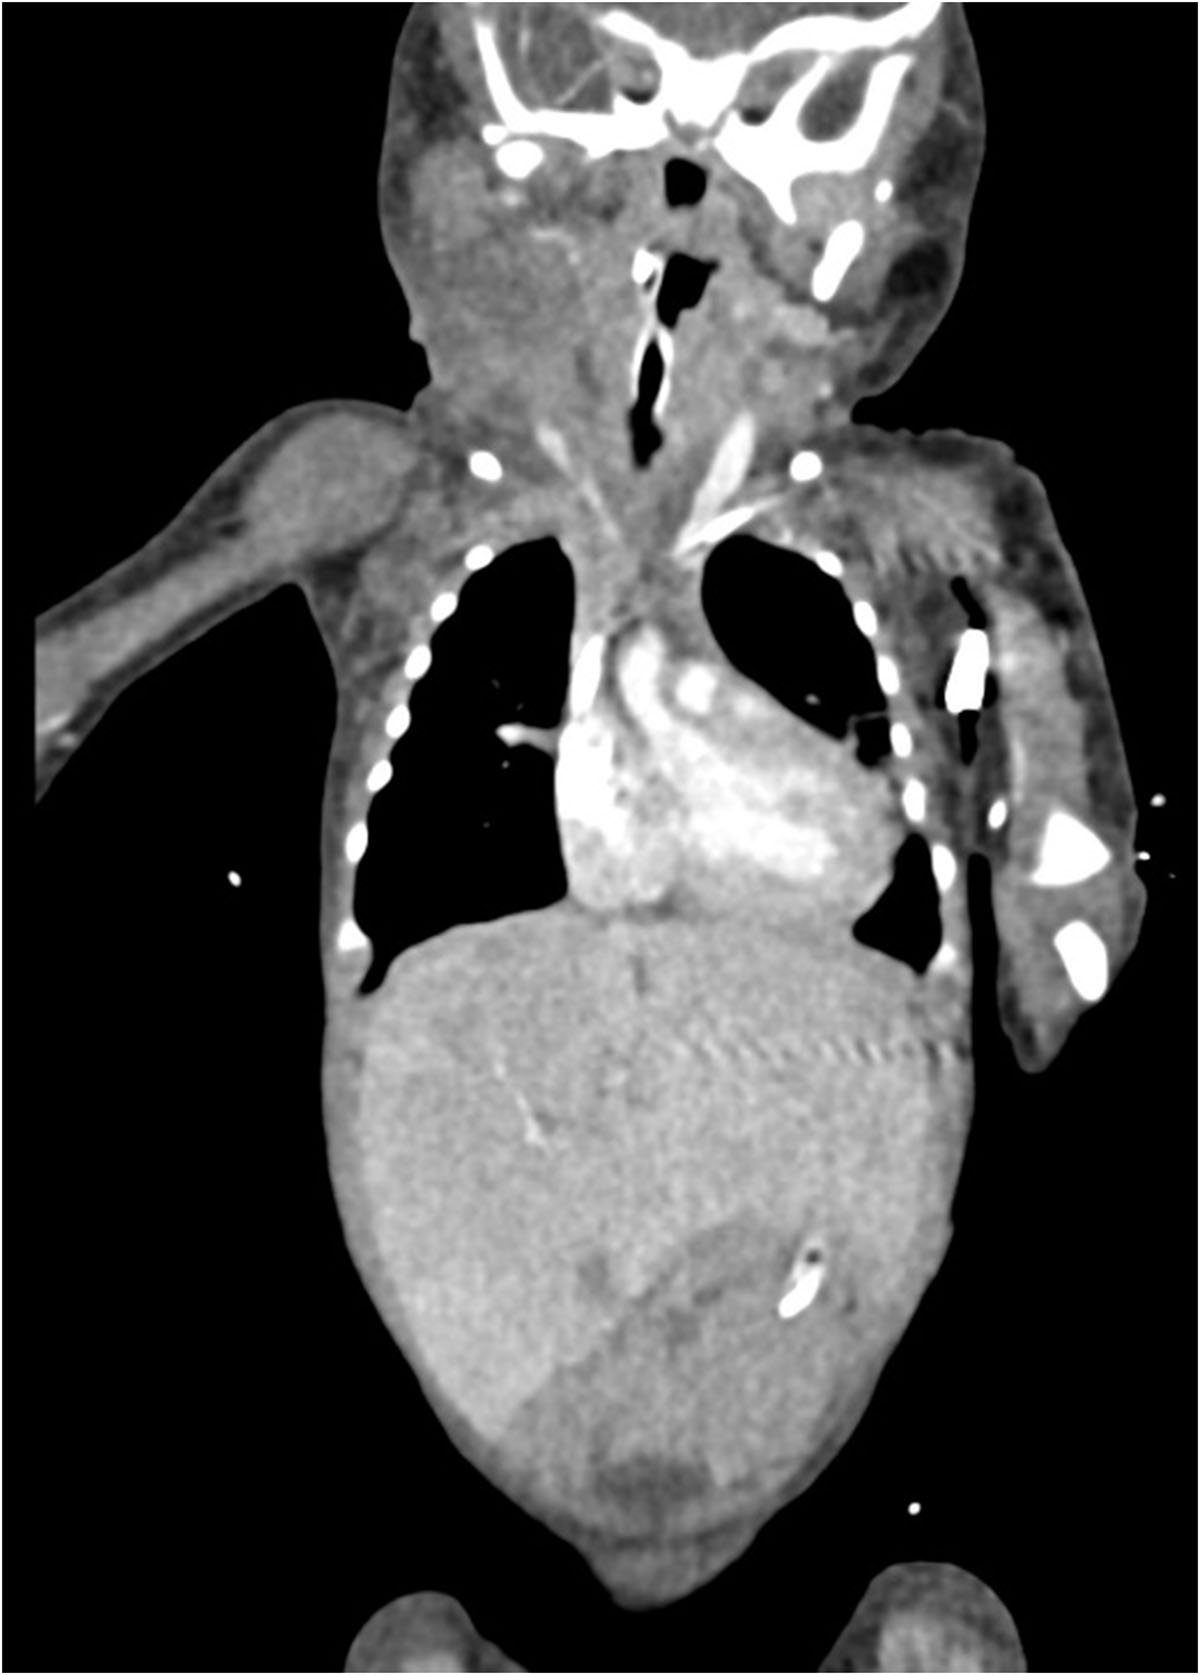

Se identifica imagen redondeada, de bordes lobulados, dependiente de tejidos blandos, heterogénea por áreas sólidas y quísticas internas, así como algunas calcificaciones irregulares dispersas, tras la aplicación de medio de contraste con realce ávido heterogéneo en sus porciones sólidas, con dimensiones de 89.3×88.3×80.9 mm y volumen de 333.6 cc; localizada en los espacios masticador, parotídeo, parafaríngeo, submandibular, visceral, supraesternal, perivertebral bucal y cervical posterior derechos.5. IMÁGENES

La tomografía computarizada (TC) muestra una masa compleja bien delimitada, con componentes sólidos, quísticos, calcificados y grasos, hallazgo característico de los teratomas maduros. La TC permite valorar la relación con estructuras vasculares, la vía aérea y el mediastino, siendo útil en la planificación quirúrgica.

La resonancia magnética (RM) constituye la técnica de elección para la evaluación anatómica detallada, debido a su superior contraste tisular y la ausencia de radiación ionizante. En secuencias ponderadas en T1 se observan focos hiperintensos por grasa o hemorragia, mientras que en T2 predominan las áreas quísticas hiperintensas [1,5]. Además, la RM define la extensión hacia el mediastino o la base del cráneo y permite valorar el desplazamiento o compresión traqueal, aspectos críticos para el manejo perinatal.

El tratamiento consiste en la resección quirúrgica completa, la cual puede requerir abordajes multidisciplinarios, especialmente cuando existe compromiso de la vía aérea. En casos diagnosticados prenatalmente, se recomienda la planificación del parto mediante la técnica EXIT (Ex UteroIntrapartumTreatment), que permite asegurar la ventilación del recién nacido antes de cortar el cordón umbilical [1,3].